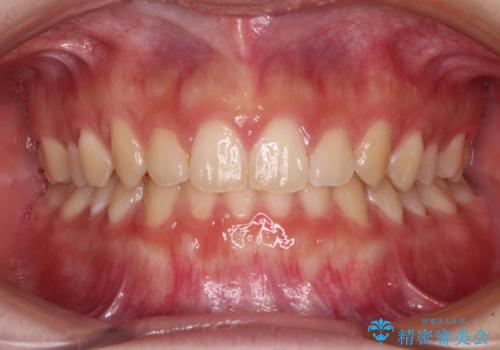

前歯のすきっ歯を治したい インビザラインによる矯正治療

- 上顎前歯の隙間を気にして来院された患者様です。

目立たない装置を希望とのことで、インビザラインを用いて矯正治療を行うこととしました。

一度インビザラインのマウスピースセットをお渡しすると1年以上来院されず、マウスピースを破損したり紛失したりすると来院されるというのんびりとしたペースで治療を行ったため、4年間という長期にわたる治療となりました。

最終的には隙間は全て閉じ、綺麗な仕上がりとなりました。